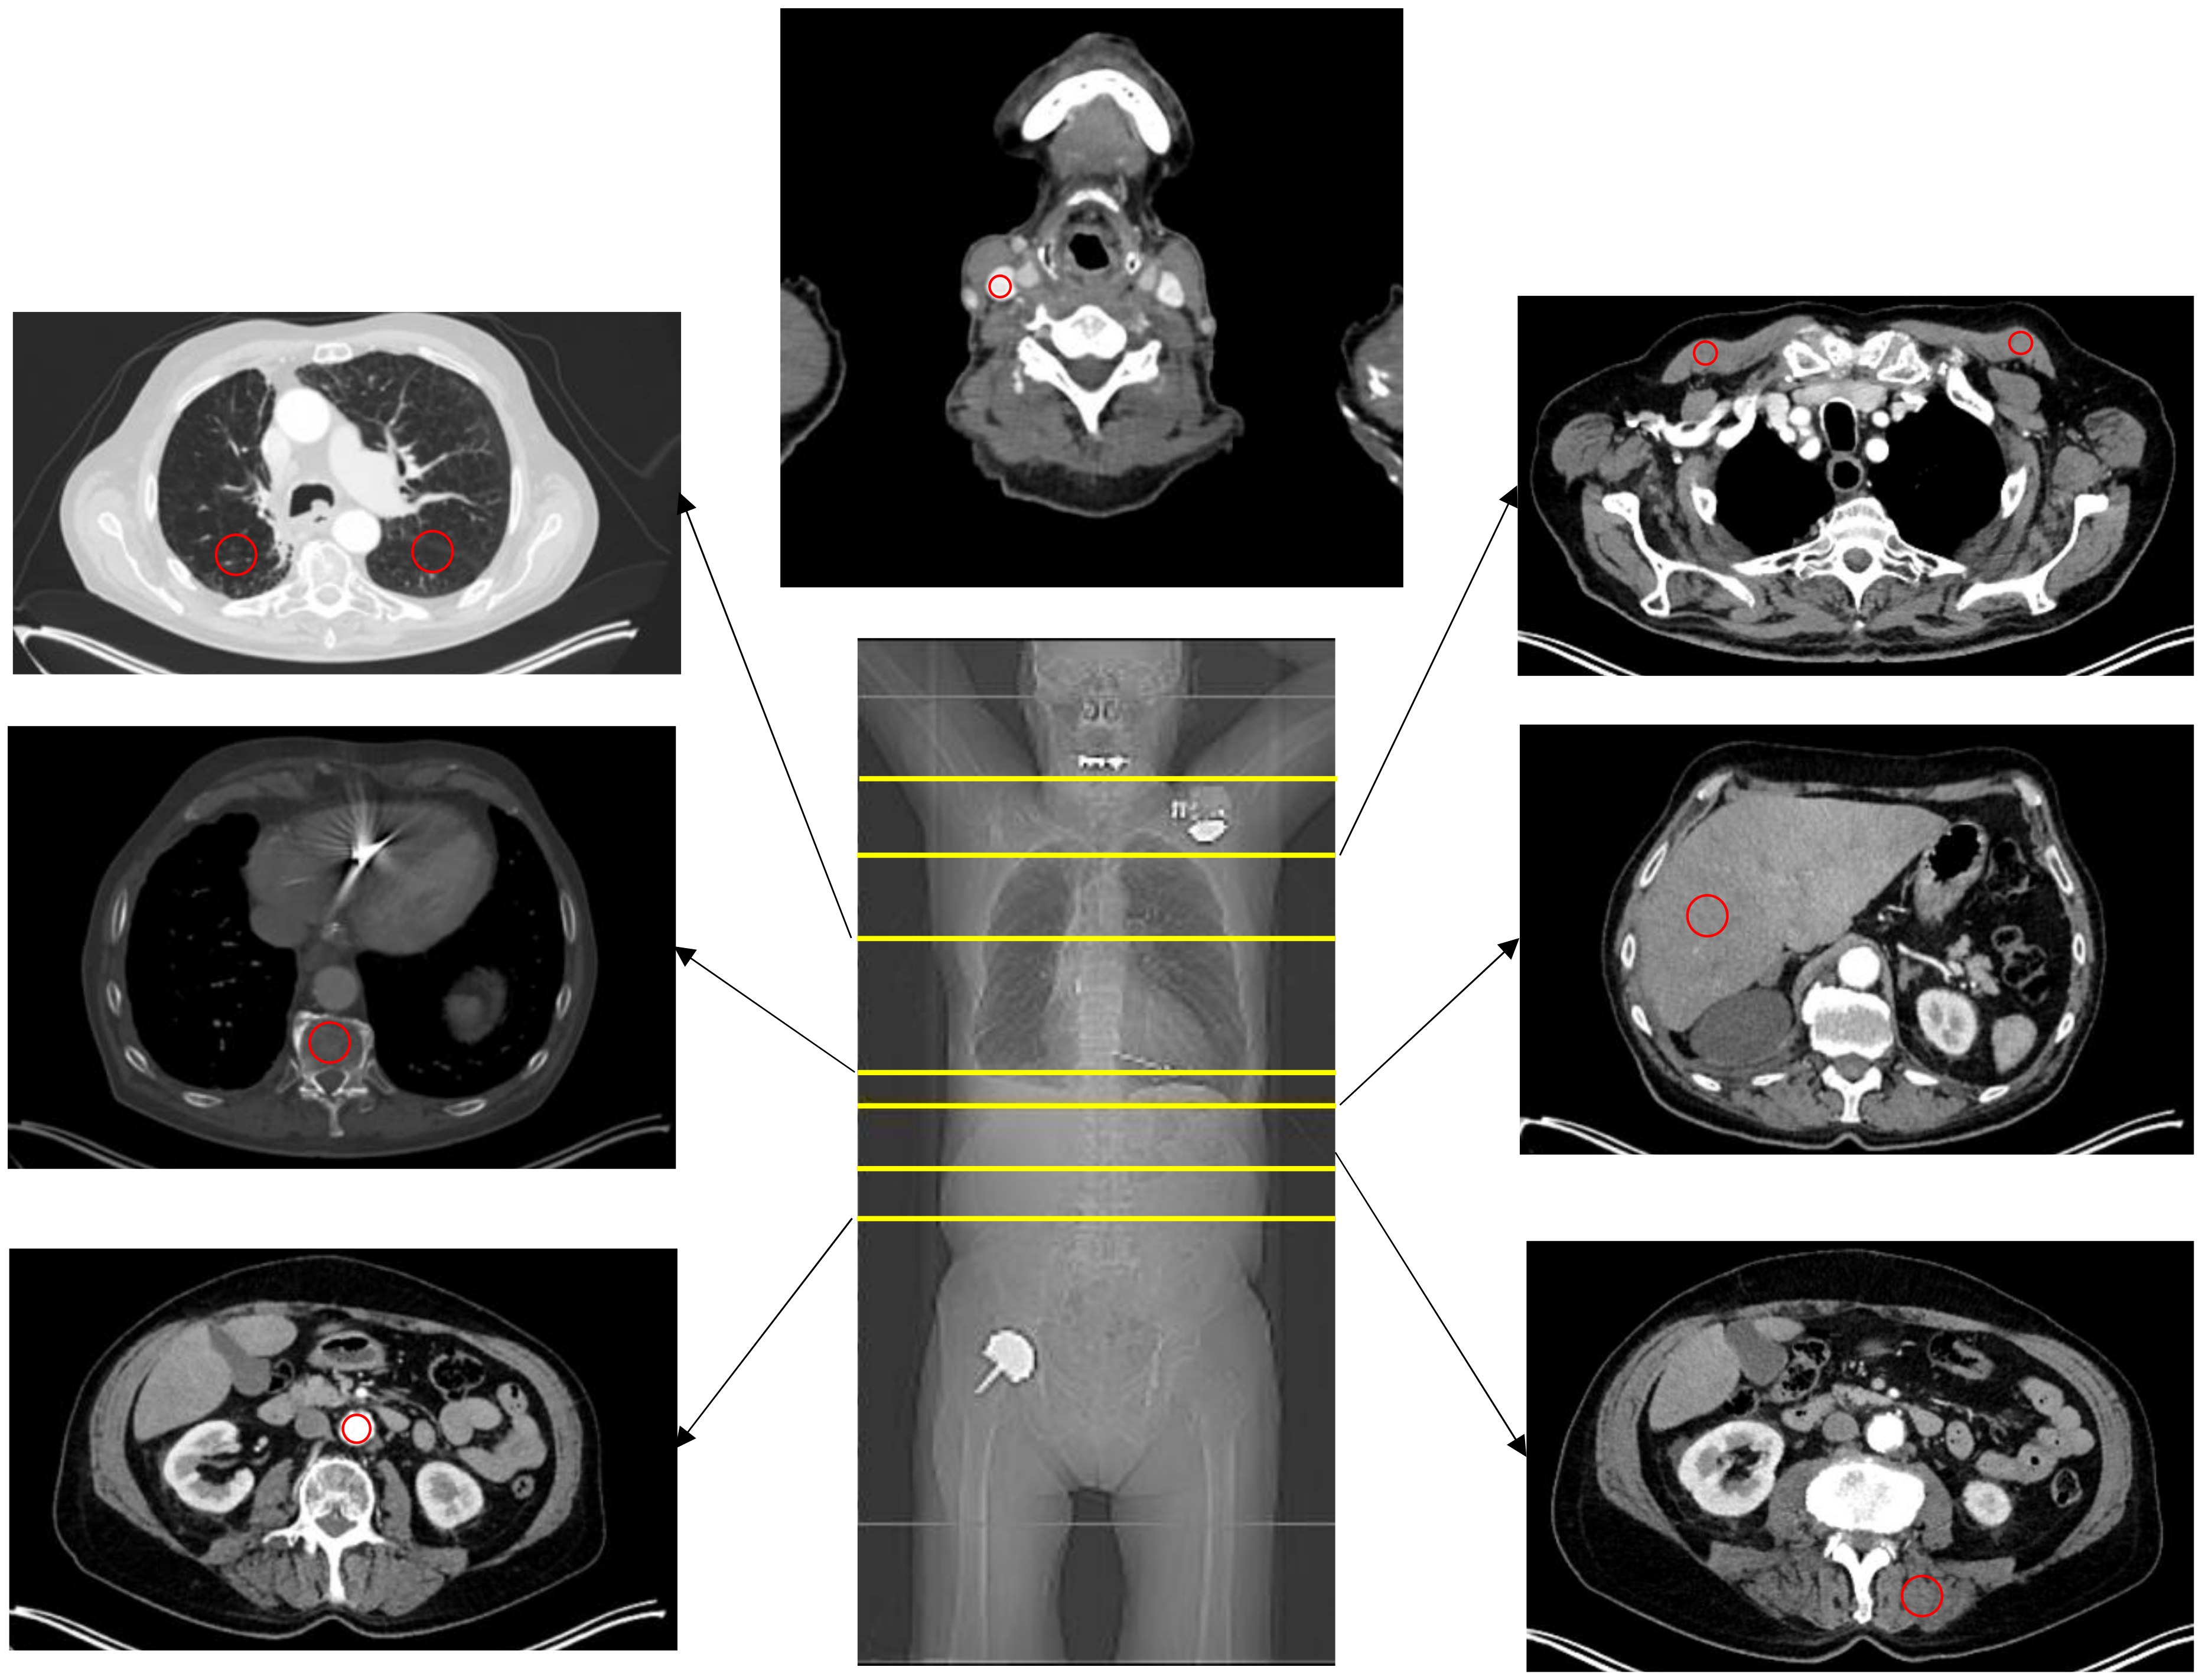

Average Hounsfield Unit (HU) values in the CT images as well as SUVmean and SUVmax values in PET images were measured for each ROI. Measurements were conducted in the liver (segment 6), lung (right and left lower lobe, segment 6), descending aorta, thoracic vertebral body 12, autochthonous back muscles, pectoral muscles, and internal jugular vein (Figure 2). The respective ROI was placed outside of artifacts and in morphologically inconspicuous areas.

Figure 2.

Overview of different measurement localizations. The red circle indicates the localization of the measurements.